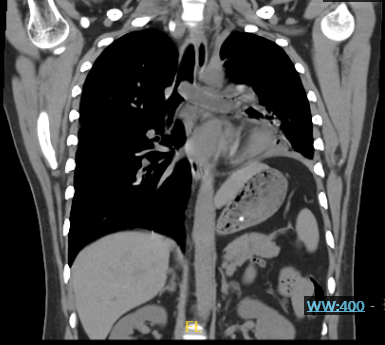

在呼吸科医生赶到前,急诊科接诊医生已为患者紧急完善了初步的化验检查并及时给予对症处理,刘亭威查看CT检查结果,提示患者主气管及左主支气管内可见条状实性病变,管腔严重狭窄,左肺周围见炎性病变。这些改变正是导致患者急性呼吸困难的原因。

CT可见肿物阻塞左主支气管(红框所示),并延伸至隆头上主气管处,阻塞部分右主支气管开口